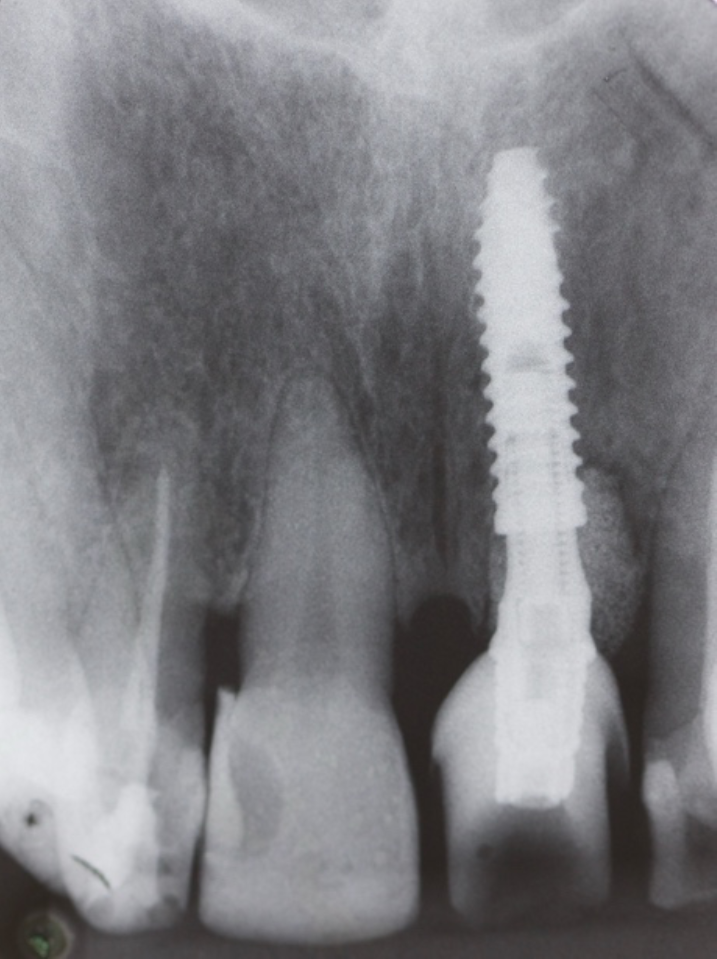

O objetivo deste relato de caso é mostrar a utilização do implante de diâmetro reduzido em região anterior de maxila com limitação óssea, respeitando a anatomia do processo alveolar e consequentemente utilizando um componente angulado para corrigir a posição da saída do parafuso para confecção de uma prótese aparafusada.

O planejamento do tratamento deve envolver uma avaliação abrangente da saúde bucal do paciente, incluindo a avaliação da densidade óssea e a disponibilidade de osso adequado para a estabilidade do implante. A colocação do implante em um posicionamento tridimensional perfeito e a estabilidade primária adequada são essenciais para o sucesso a longo prazo.

Conforme discutido na literatura, a colocação imediata de implantes na zona estética requer que o clínico tenha conhecimento e experiência em diversas áreas. Isso inclui diagnóstico estético, técnicas de extração minimamente invasivas, procedimentos cirúrgicos plásticos orais (por exemplo, enxerto de tecidos duros e moles) e colocação de implantes tridimensionais (3D) precisos com o uso de um implante mais estreito (3,3 mm a 4,3 mm), o que garante um espaço vestibular de pelo menos 2 a 3 mm adjacente à parede do alvéolo bucal intacto. Isso pode ser pré-planejado com uma análise cuidadosa através de exames de imagem para uma melhor compreensão do plano restaurador. O uso de técnicas avançadas de imagem, como a tomografia computadorizada de feixe cônico (CBCT), pode auxiliar no planejamento preciso do tratamento e na colocação do implante.

O planejamento no tratamento de implante imediato deve incluir uma avaliaçãocompleta do alvéolo de extração, osso circundante e tecidos moles. Essa avaliação ajuda a determinar o tamanho, o tipo e a técnica de colocação do implante.